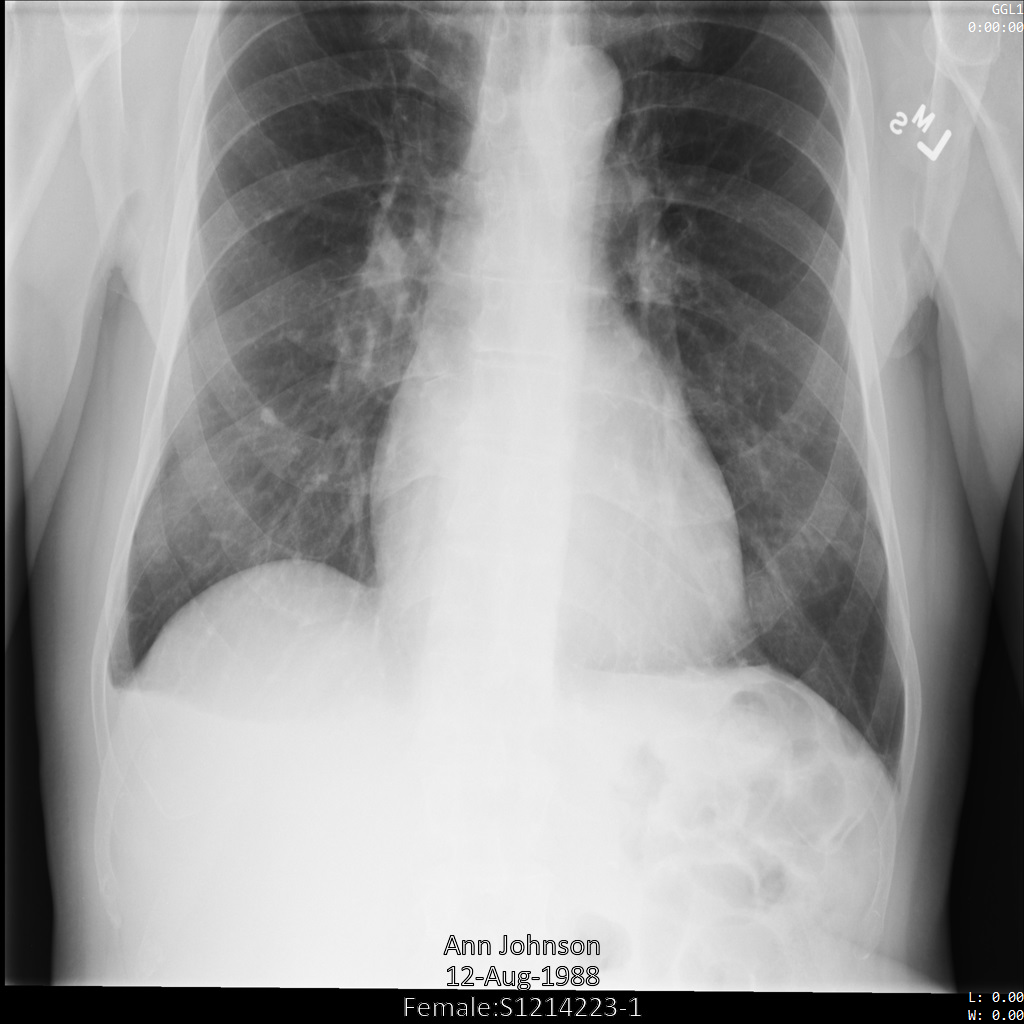

以下各節提供範例,說明如何使用各種方法去識別 DICOM 資料。每個樣本都會提供去識別化圖片的輸出內容。每個範例都會使用下列原始圖片做為輸入內容:

您可以比較各項去識別化作業的輸出圖片與原始圖片,瞭解作業效果。

將圖片提交給 Cloud Healthcare API 後,圖片會如下所示。雖然圖片頂端角落顯示的中繼資料已遭塗銷,但圖片底部的內建受保護健康資訊 (PHI) 仍存在。如要一併移除內建文字,請參閱「從圖片中遮蓋內建文字」。